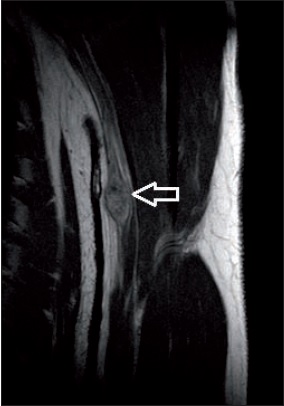

La resonancia magnética (RM) es el método electivo de exploración. Puede distinguir perfectamente las características de la tumoración y su relación con el propio nervio afectado y permite observar si interrumpe o no su continuidad (Fig. 2). En las imágenes de cortes transversales, las zonas hipointensas en secuencia T2 tienen correlación histológica con las zonas tipo Antoni A (cuerpos de Verocay). Aunque no es necesario para el diagnóstico, mediante la inyección intravenosa de contraste se puede tener una idea aproximada del grado de vascularización tumoral.(14)